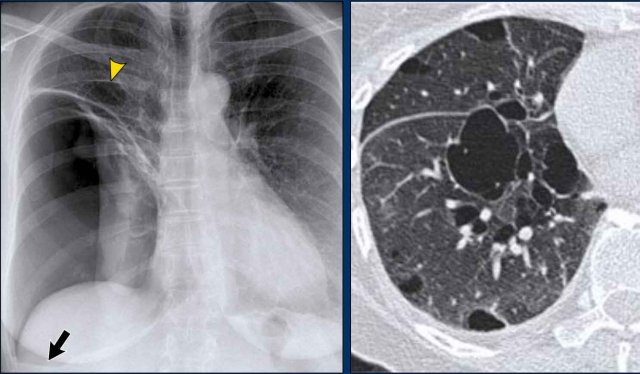

Hidden Areas (3): Pneumonia Below the Diaphragm

In this case, a pneumonia was primarily located below the right diaphragmatic dome (yellow arrow), within the posterior basal segment of the right lower lobe.

- On the lateral view, there is an increase in opacity over the lower thoracic vertebrae, indicating lower lobe consolidation (arrow).

- Again, image magnification may be necessary for adequate assessment.